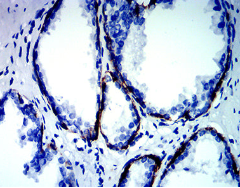

KRT13 Mouse Monoclonal antibody[7D7B3]

The protein encoded by this gene is a member of the keratin gene family. The keratins are intermediate filament proteins responsible for the structural integrity of epithelial cells and are subdivided into cytokeratins and hair keratins. Most of the type I cytokeratins consist of acidic proteins which are arranged in pairs of heterotypic keratin chains. This type I cytokeratin is paired with keratin 4 and expressed in the suprabasal layers of non-cornified stratified epithelia. Mutations in this gene and keratin 4 have been associated with the autosomal dominant disorder White Sponge Nevus. The type I cytokeratins are clustered in a region of chromosome 17q21.2. Alternative splicing of this gene results in multiple transcript variants; however, not all variants have been described.

IHC    1/200 - 1/1000